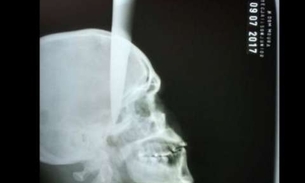

Após discussão em bar, homem fica com faca cravada na cabeça

Um homem de 35 anos teve uma faca cravada na cabeça após descutir com a pessoa com quem bebia em um bar na zona rural de...